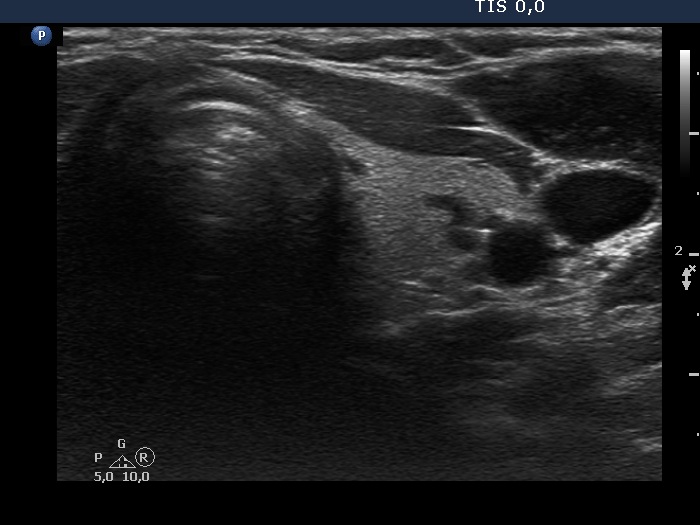

100 consecutive cases of papillary cancer - case 071 (ultrasonographic picture 11)

Right lobe, longitudinal scan

Left lobe, transverse scan. The hypoechoic areas have minimal if any significance.